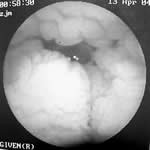

图2 胶囊内镜:空肠黏膜水肿,脑回样改变。